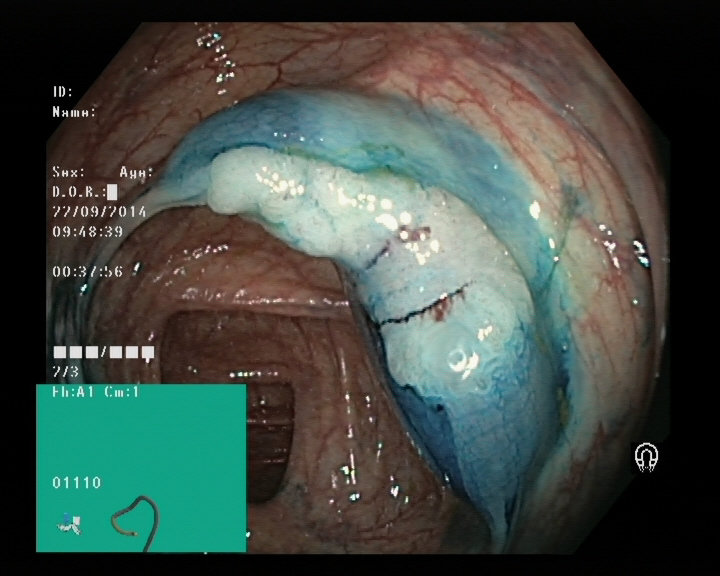

Image of a polyp from a colonoscopy

Gastroscopy and colonoscopy

Dyed lifted polyps

Dyed resection margins